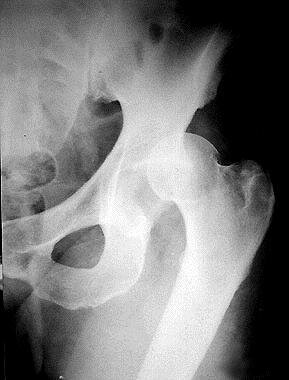

Вывих бедренной кости в тазобедренном суставе  – это серьезная травма, происходит смещение головки бедренной кости за пределы вертлужной впадины - более 5% от числа всех вывихов.

▪️Рентген сустава (для исключения костных повреждений и уточнения расположения головки бедра, рентген необходим в двух проекциях)